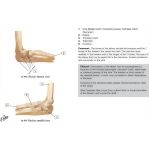

Bones of Elbow

Bones of Elbow

Labeled - Cleland Ortho Clinical Exam 1E